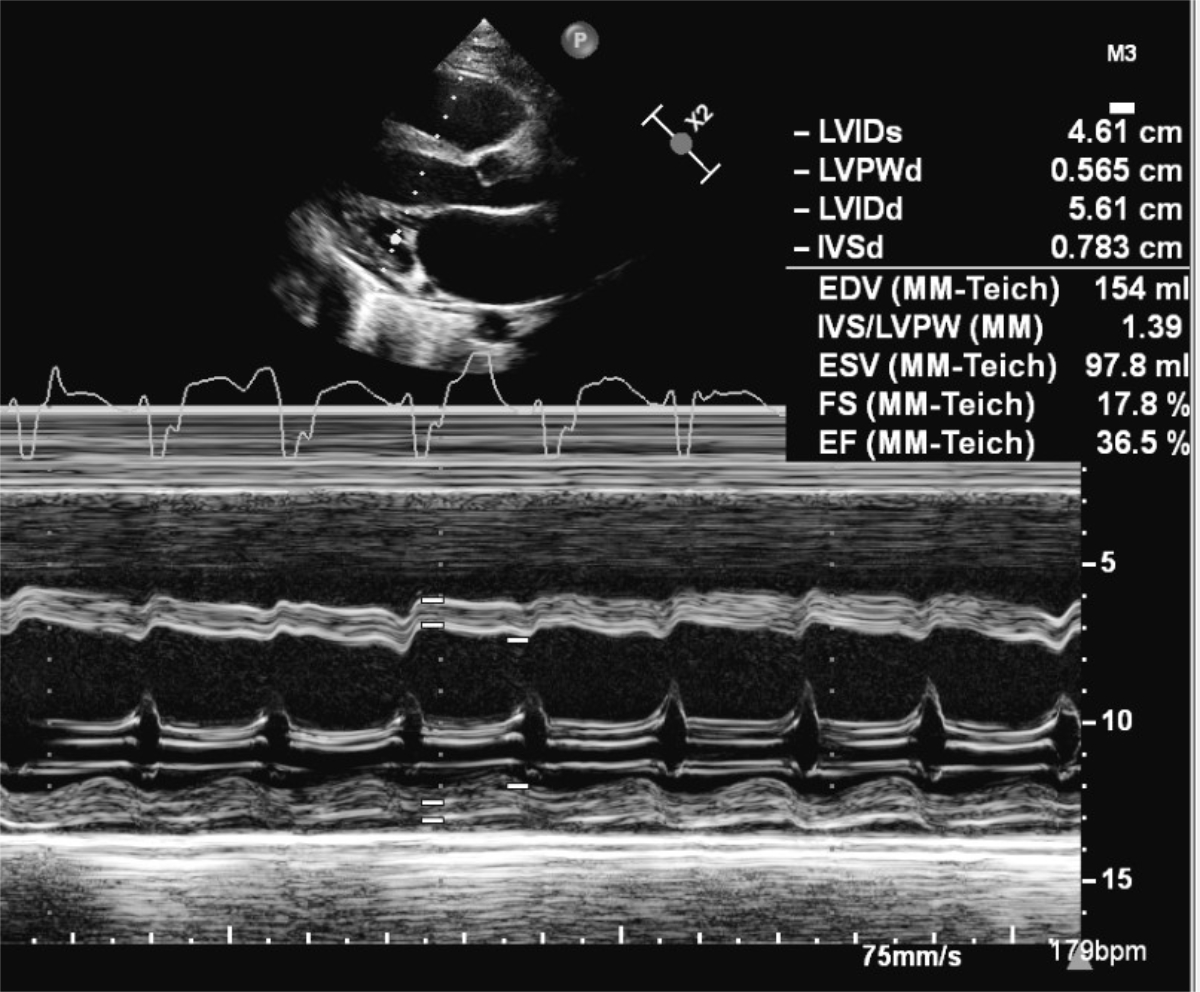

Thirteen days after the positive PCR test, he was admitted to our cardiac paediatric intensive care unit in decompensated cardiogenic shock due to a monomorphic ventricular tachycardia (fig. 1) and moderately to severely reduced biventricular cardiac function with a biplane left ventricular ejection fraction of 20%, right ventricular fractional area change of 12%, and fractional shortening of 18% (fig. 2). He was afebrile and the second nasophyrangeal swab for SARS-CoV-2 PCR was still positive after admission. On admission troponin-T was 48 ng/l (reference <14 ng/l), creatinine kinase (CK) 201 U/l (<168 U/l), CK-MB 7.3 µg/l (<6.2 µg/l), and N-terminal-pro-B-type natriuretic peptide (NT-pro-BNP) 10,738 ng/l (<360 ng/l). There were no signs of thrombocytopenia, increased C-reactive protein, and no elevation or decrease of white blood cells or abnormalities in the white blood cells subsets. The clinical status showed no lymphadenopathy, conjunctivitis, mucus membrane changes, rash, or swollen hands and feet. The ventricular tachycardia was recurrent and required electric cardioversion on three occasions within the first 24 hours, in addition to amiodarone therapy. The severely reduced biventricular myocardial function led to progressive pulmonary oedema, pericardial and pleural effusions, and oxygenation failure requiring intubation, high ventilator pressures, inhaled nitric oxide, and bilateral chest drains. A suspected secondary bacterial pneumonia due to the severe clinical (septic) course was treated empirically for 5 days with antibiotics, although cultures remained negative. He was not given additional antiviral therapy due to limited evidence and spontaneous clinical recovery. Progressive low cardiac output with cardiogenic shock and multi-organ dysfunction (acute renal failure RIFLE-I [11], liver dysfunction with coagulopathy) required high-dose inovasodilators. On day 4, creatinine kinase (maximum 2040 U/l) and myoglobin (maximum 669 ng/ml) were at their highest level. The following ECG revealed altered repolarisation (negative T wave up to V6), but no signs of acute infarction. The myocardial function measured by echocardiography improved rapidly, with a left ventricular ejection fraction of 40–50% within 48 hours of admission. After 5 days of inotropic treatment and mechanical ventilation he was transferred to the cardiac ward under treatment with oral diuretics, enalapril, and amiodarone.

Figure 2 Transthoracic 2D echocardiography at admission showed severe reduced left ventricular function on M-mode with a fractional shortening of 18%.